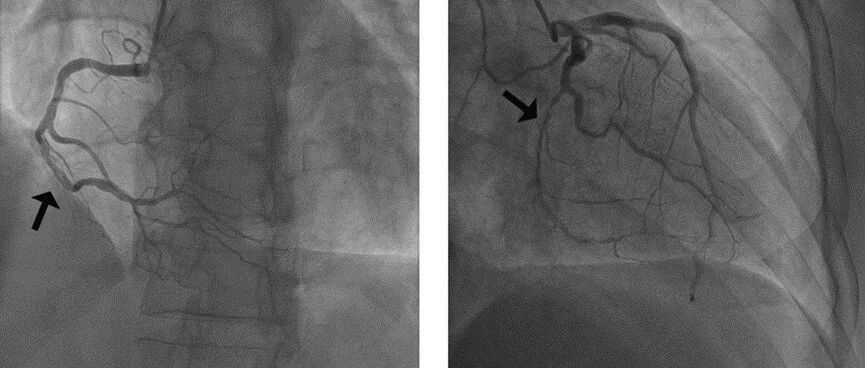

病例 | 中年男性胸痛+肌钙蛋白升高+造影无斑块,竟是多支SCAD!男性中罕见,你会如何追问病因? 心在线 · 公众号 · · 3 月前 · |